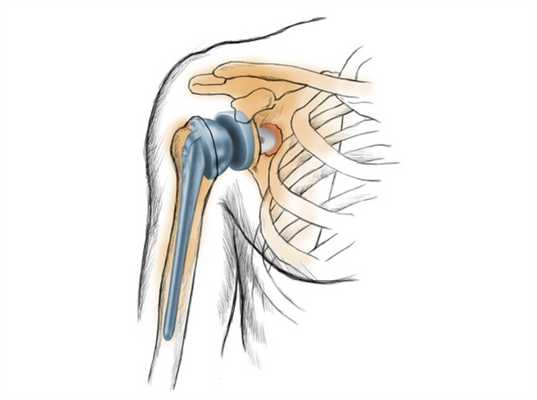

Полная замена илитотальное эндопротезирование плечевого сустава. Стержень плечевого протеза может закрепляться на цементе или бесцементно. © Gelenk-Klinik

Полная замена или тотальное эндопртезирование плечевого сустава. Стержень плечевого протеза может закрепляться на цементе или бесцементно.

Тотальное эндопротезирование плечевого суставного сочленения

Этот способ для проведения замены используют чаще других. Чтобы осуществить тотальное эндопротезирование плеча, надо полностью заменить его структуры. Для этого удаляют все образования - головку, кости, впадину.

В зону, где была суставная головка, устанавливают протез с наличием шаровидного элемента, который расположен на ножке. Ее помещают внутрь костного канала. В месте, где была впадина, укрепляют пластмассовую часть конструкции, имитирующую поверхность хряща. Ножку протеза имплантируют внутрь кости.

После проведения полного эндопротезирования плеча иногда ослабляется суставная губа, что приводит к развитию таких осложнений, как ограничение подвижности в пораженной зоне и болевой синдром.